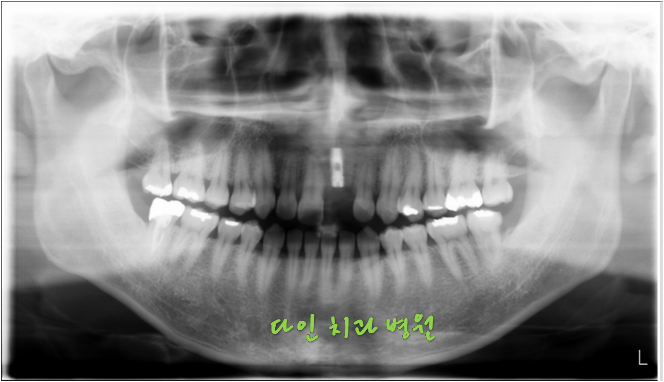

일반 엑스레이 외에도 3D CT 등 정밀 진단이 가능한 최신 의료장비를 갖추고 있는지도 살펴보아야 합니다. 잇몸 뼈를 비롯해, 혈관, 신경 위치까지 정밀하게 진단이 되어야 그에 맞춰 시술 계획을 세울 수 있기 때문이죠.